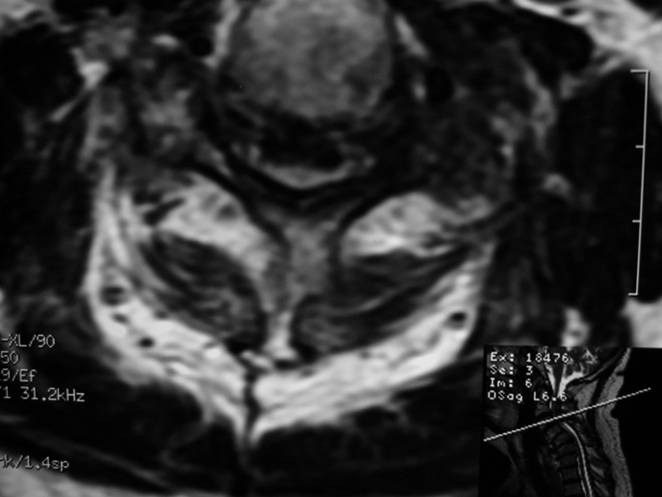

MRI